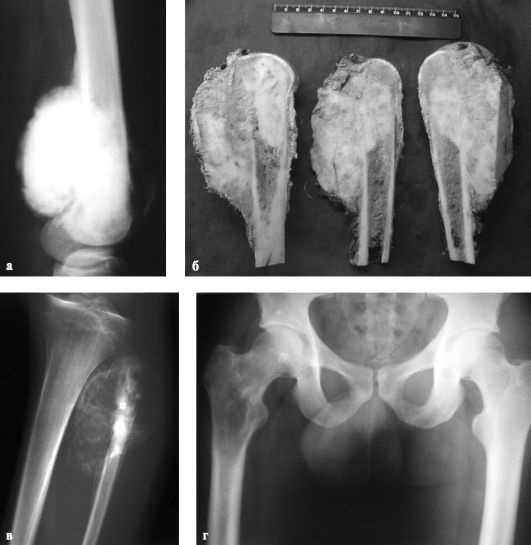

Диагностика остеосаркомы начинается с тщательного осмотра пациента и включает рентгенографию пораженной конечности, а также гистологическое исследование образцов тканей опухоли. Для выявления опухолевых клеток в других органах и тканях применяются магнитно-резонансная и компьютерная томография.

Первым шагом в терапии является химиотерапия, которая помогает уменьшить размеры опухоли и уничтожить некоторые метастазы. В этом процессе используются цитостатики. Следующим этапом является хирургическое вмешательство, в ходе которого обычно выполняется резекция пораженной кости, а затем протезирование удаленной части сустава. Полная ампутация конечности требуется лишь в случаях крупных новообразований или метастазирования опухоли в мышцы и нервные окончания.

Во время операции удаляется не только первичный очаг опухоли в тазобедренной кости, но и крупные метастазы в других органах. Также обязательно удаляются регионарные лимфоузлы. После хирургического вмешательства пациенту снова назначается химиотерапия, направленная на уничтожение оставшихся опухолевых клеток и предотвращение дальнейшего распространения метастазов.